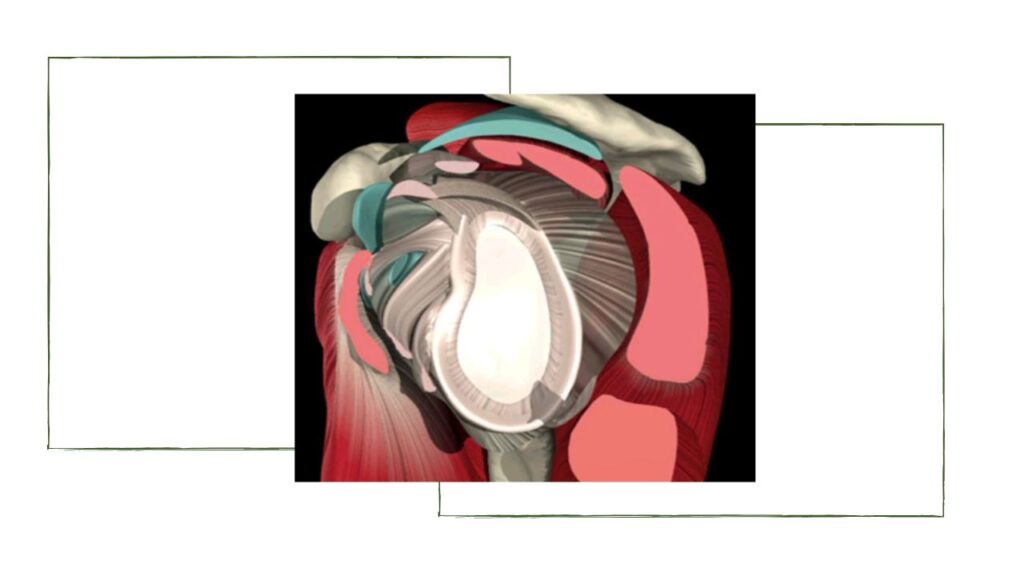

Como forma de diminuir essa instabilidade intrínseca, existem diversos mecanismos de estabilização estáticos e dinâmicos. Os estáticos são: versão glenóide/umeral, labrum, estruturas cápsulo-ligamentares, pressão intra-articular negativa e propriocepção. Já os dinâmicos são: manguito rotador, musculatura escapulo-torácica e cabeça longa biceps.

A luxação ocorre principalmente no paciente jovem, dos 15 aos 40 anos de idade, e a complicação mais frequente é a recidiva, ou seja, o ombro se torna instável e volta a luxar em algumas posições e até dormindo. Em outros pacientes, não há a luxação completa, com sub-luxações, e a queixa pode ser de instabilidade ou de fraqueza súbita com a sensação de braço paralisado. Acima dos 40 anos de idade, pode ocorrer a lesão do manguito rotador como lesão associada.